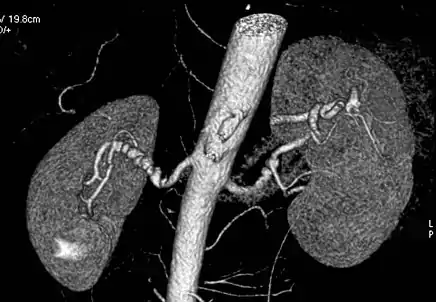

Aorta and great arteries

CTA can be used in the chest and abdomen to identify aneurysms in the aorta or other major blood vessels. These areas of weakened blood vessel walls that bulge out can life-threatening if they rupture. CTA is the test of choice when assessing aneurysm before and after endovascular stenting due to the ability to detect calcium within the wall.[3] Another positive of CTA in abdominal aortic aneurysm assessment is that it allows for better estimation of blood vessel dilation and can better detect blood clots compared to standard angiography.[4]

Visualization of blood flow in the renal arteries (those supplying the kidneys) in patients with high blood pressure and those suspected of having kidney disorders can be performed using CTA. Stenosis (narrowing) of a renal artery is a cause of hypertension (high blood pressure) in some patients and can be corrected. A special computerized method of viewing the images makes renal CT angiography a very accurate examination.[6] CTA is also used in the assessment of native and transplant renal arteries.[3] While CTA is great for imaging of the kidneys, it lacks the ability to perform procedures at the same time. Thus traditional catheter angiography is used in cases of acute renal hemorrhage or acute arterial obstruction.[2]